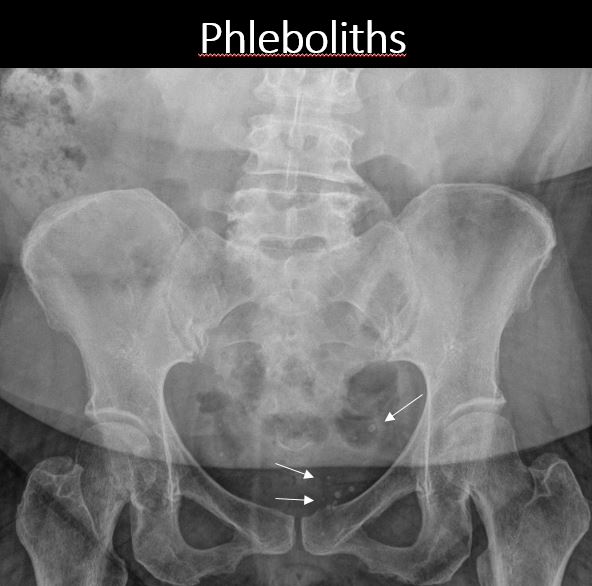

There are calcified phleboliths in the pelvis. |

No | NA |